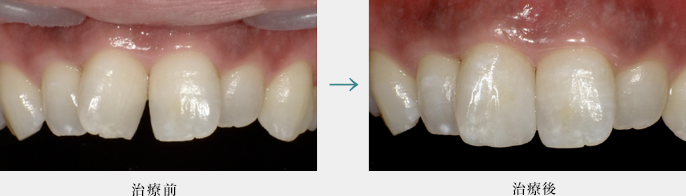

ダイレクトボンディングにより前歯の隙間を改善

ダイレクトボンディングは歯を大きく削らずに直接口腔内で材料を接着硬化させることで、歯の隙間や形態を修復する方法です。

ダイレクトボンディング